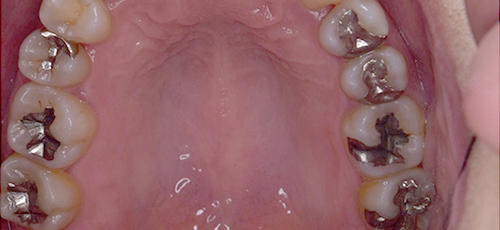

二次虫歯除去の症例

Case.1

銀歯下に潜んだ

虫歯の二次治療

保険治療で虫歯治療後の被せ物・詰め物で使用される銀歯(金銀パラジウム)は、二次虫歯のリスクがあります。原因は多くありますが、劣化などにより詰め物(インレー・アンレー)に隙間が生じ、その隙間に虫歯菌が入り込むことにより、二次虫歯となるケースがあります。

保険適応外(自由診療)のセラミックなどの強度あり、親和性の高い詰め物へ替えるという選択肢や、何よりも早期発見・早期治療が二次虫歯リスクを軽減することが可能ですので、定期検診が一番の予防対策となります。歯医者へは、こまめに通う習慣をつけましょう。